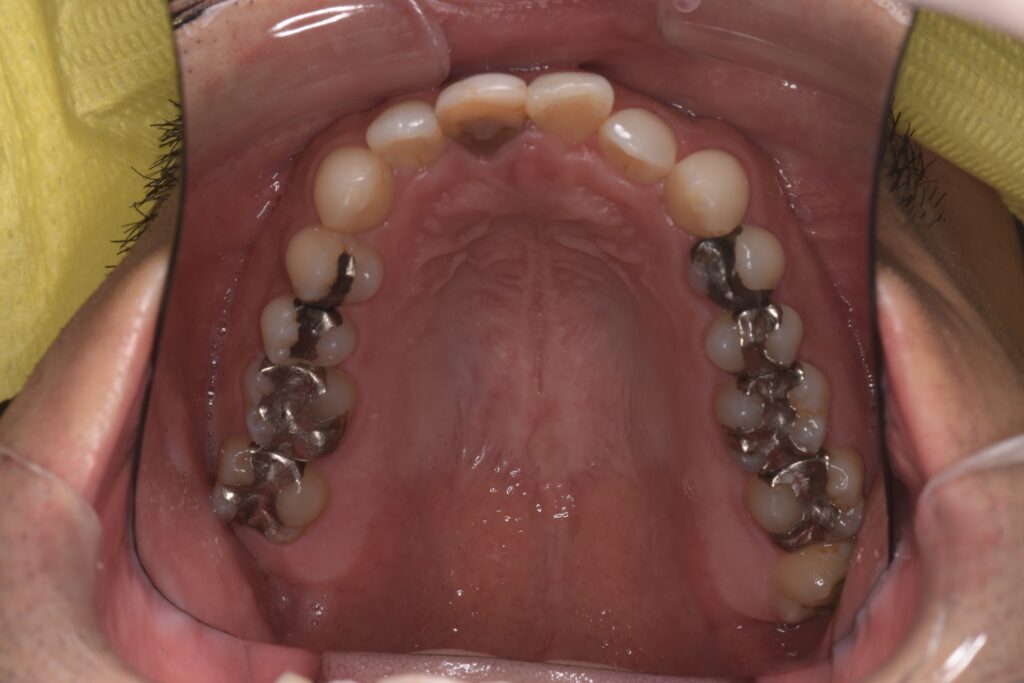

以下の症例写真例は、40代男性の症例です。

前歯のがたつきを改善するためにインビザラインによる矯正とセラミックインレー、根管治療を行い、金属を使わないメタルフリー治療を実施しました。

見た目と機能の両面で大きく改善している様子がわかります。

<術前の症例写真>